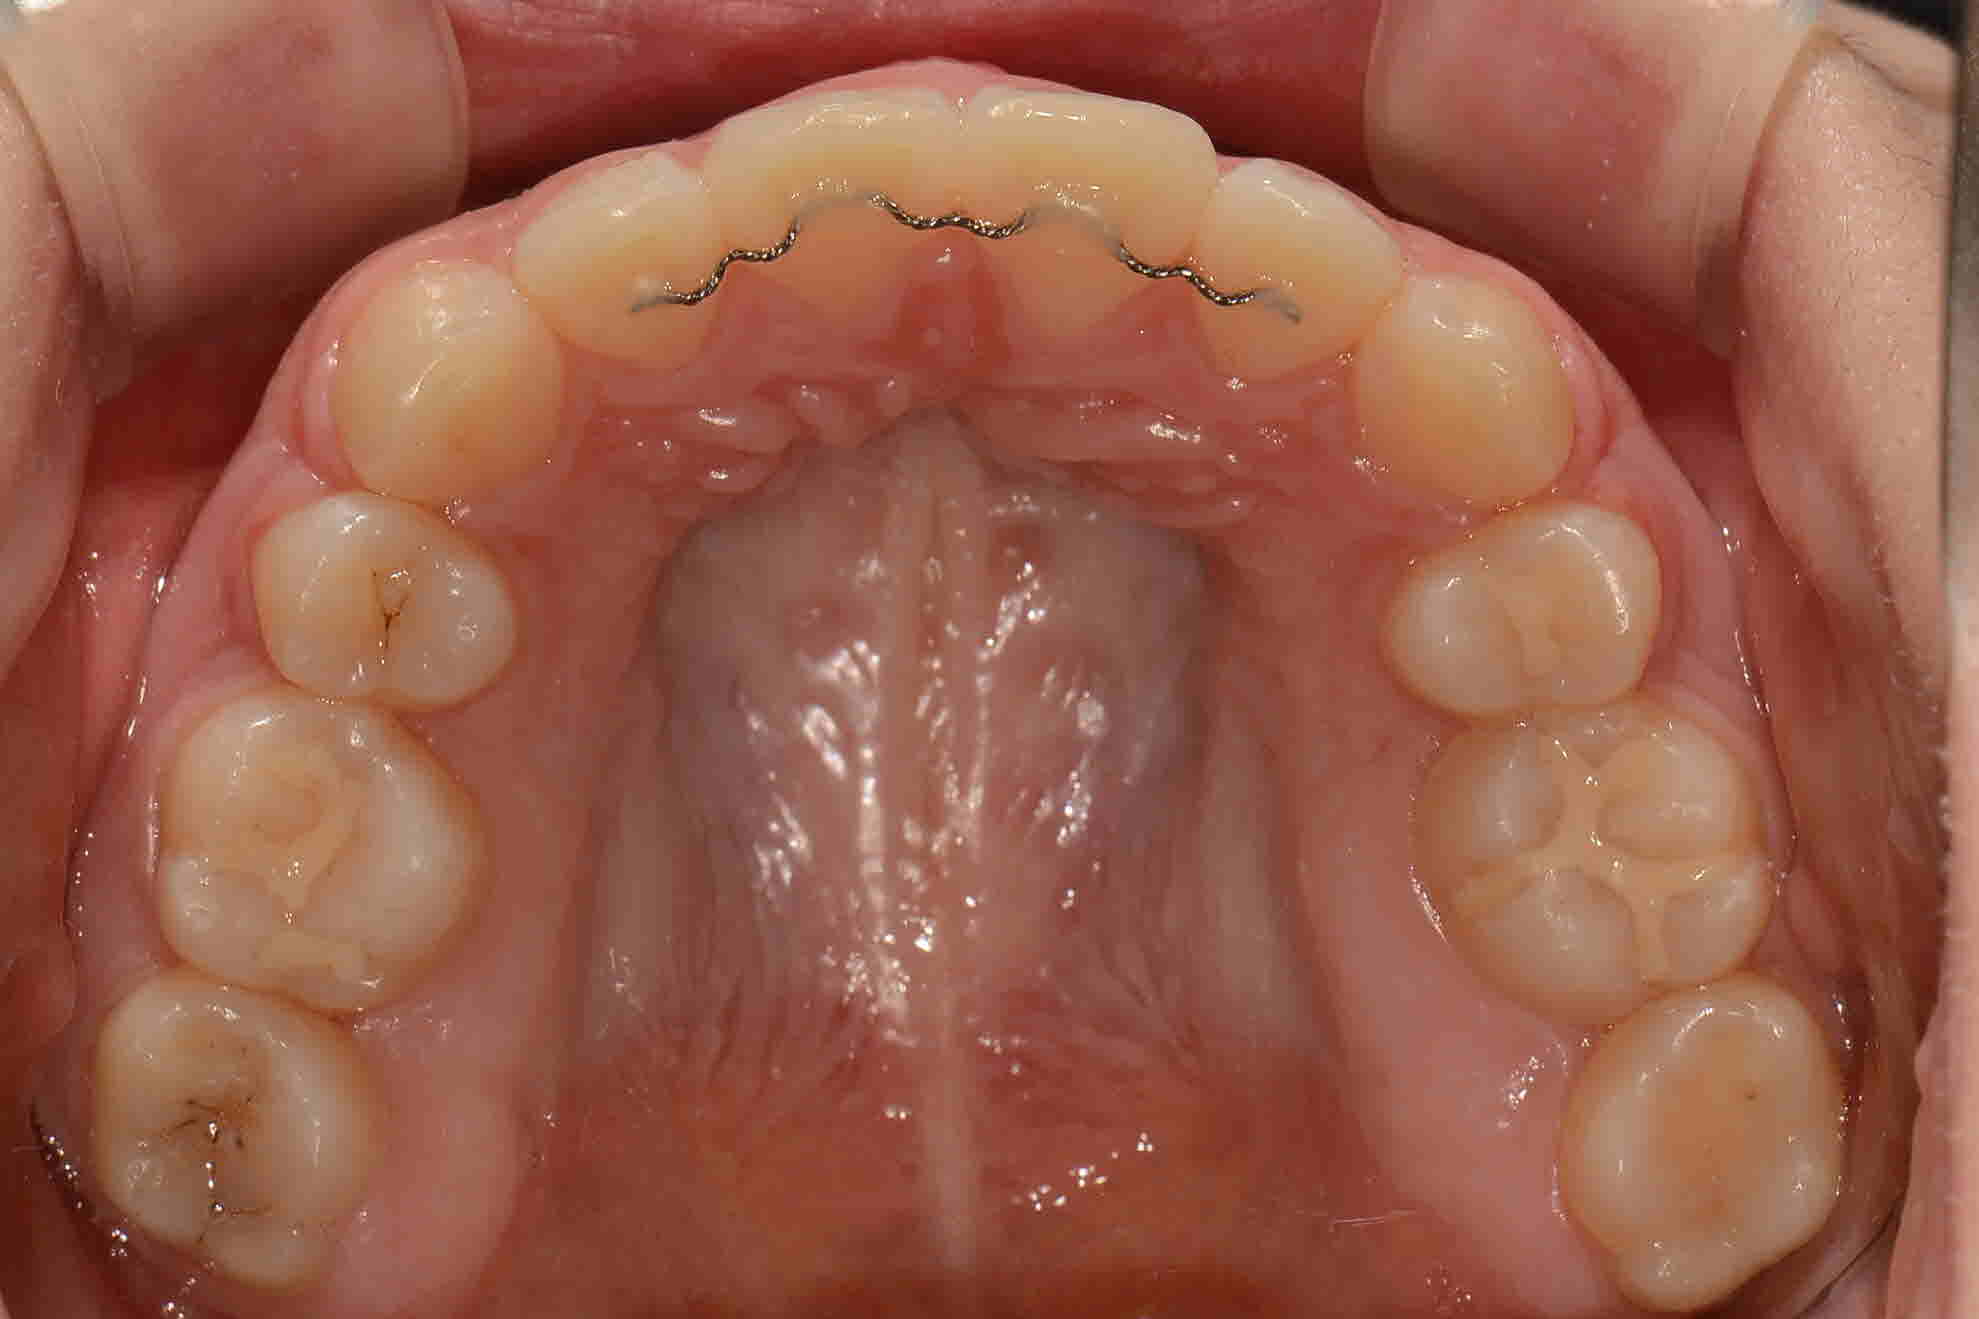

교정완료 교합면